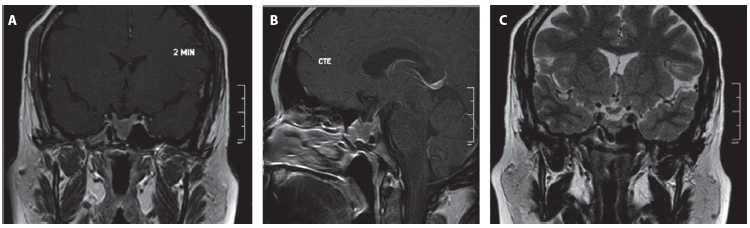

Ante la evidencia de compresión quiasmática y el riesgo de compromiso visual se planteó como primera opción el manejo quirúrgico, que no fue aceptado por la paciente. Se optó como alternativa de manejo una prueba terapéutica con cabergolina en dosis de 0,5 mg semanales con buena tolerancia. Después de 6 meses de tratamiento se realizó una IRM, en la que se evidenció la reducción del volumen tumoral del 73 % sin contacto con el quiasma (Figura 2).

Figura 2. Resonancia de hipófisis posterior al manejo. A. Secuencia T1 contrastada, corte coronal. B. Secuencia T1 contrastada, corte sagital. C. Secuencia T2, corte coronal. Tamaño tumoral residual con diámetros: 16 mm anteroposterior x 13 longitudinal x 17 transverso; volumen de 1,7 mL.